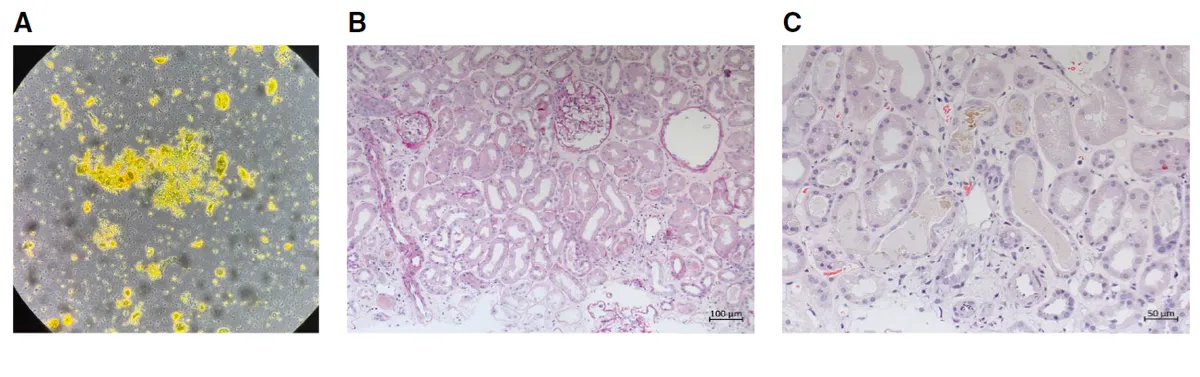

**Figura 1.** Achados urinários e histológicos da biópsia renal. (A) O sedimento urinário mostra células epiteliais tubulares, cilindros granulares corados por bile e cristais de leucina. (B) Os túbulos renais apresentam células epiteliais achatadas e perda da borda em escova (NTA). (C) Os túbulos exibem cilindros amarelo-esverdeados corados por bile (H&E).

A biópsia mostrou:

• necrose tubular aguda difusa,

• cilindros biliares verde-amarelados ocupando túbulos,

…selando o diagnóstico de Nefropatia Colêmica.